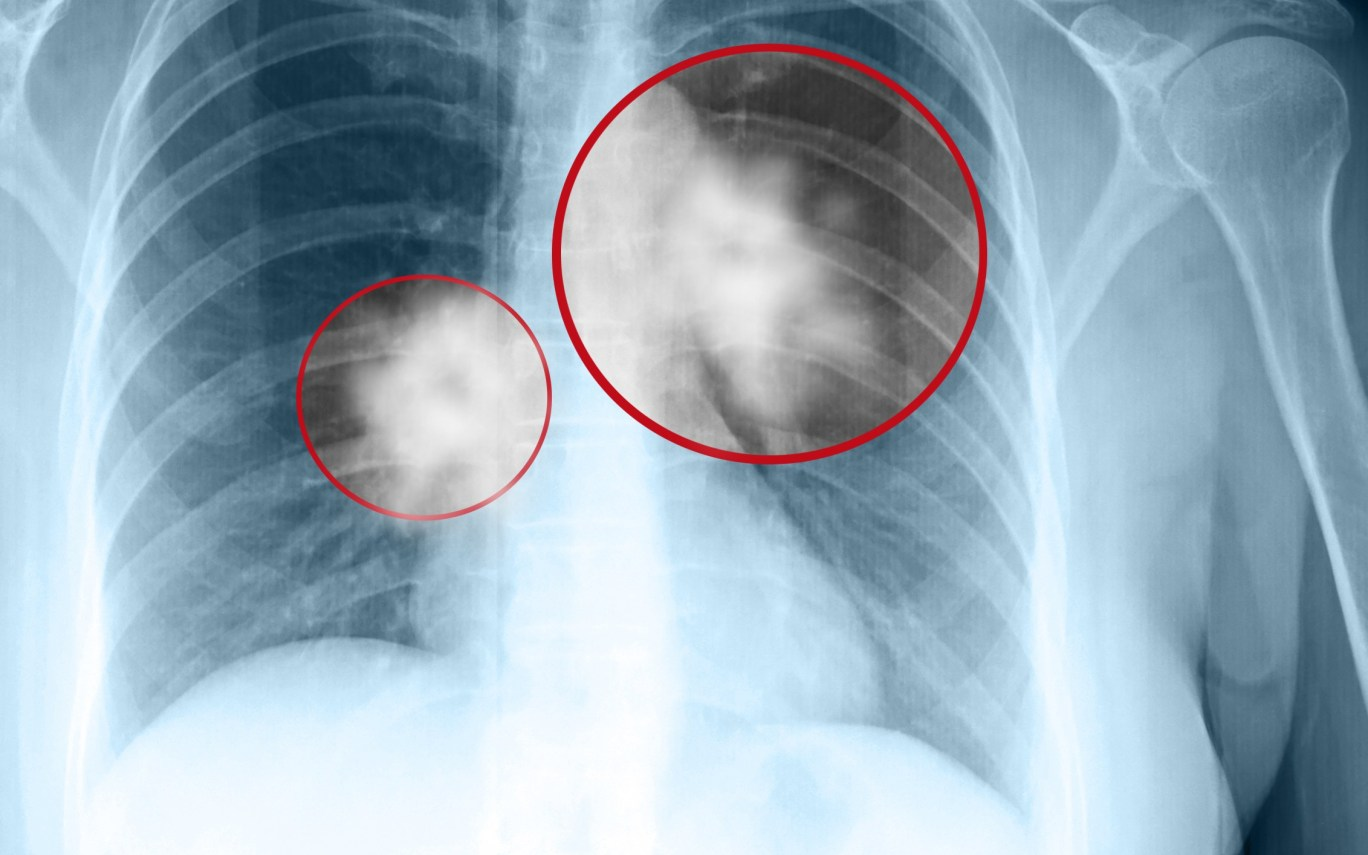

Một nghiên cứu mới hiện đã liên kết việc tiêu thụ nhiều UPF với việc tăng nguy cơ phát triển ung thư phổi. Nghiên cứu được công bố trên Thorax, phát hiện tiêu thụ nhiều UPF có liên quan đến nguy cơ mắc cả ung thư phổi không tế bào nhỏ (NSCLC) và ung thư phổi tế bào nhỏ (SCLC).

Các nhà nghiên cứu đã theo dõi những người tham gia trong trung bình 12,2 năm, trong thời gian đó có 1.706 trường hợp được chẩn đoán mắc ung thư phổi. Trong số này, 1.473 (86,3%) là NSCLC và 233 (13,7%) là SCLC.

Những người ăn nhiều UPF có nguy cơ được chẩn đoán mắc ung thư phổi cao hơn. Trong nhóm tiêu thụ UPF thấp nhất, 331 trong số 25.433 người (1,3%) được chẩn đoán mắc ung thư phổi. Trong nhóm UPF cao nhất, 485 trong số 25.434 người (1,9%) được chẩn đoán mắc ung thư phổi. Các nhà nghiên cứu kết luận, những người ăn nhiều UPF nhất có nguy cơ mắc ung thư phổi cao hơn 41% so với những người ở nhóm thấp nhất.